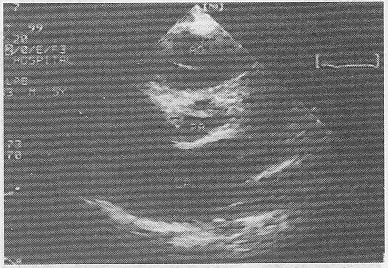

5.患者,男,30歲,常感心悸、氣促,超聲檢查如圖所示,該病例最可能的診斷是

正確答案:B 解題思路:室間隔與左室后壁非對稱性肥厚。